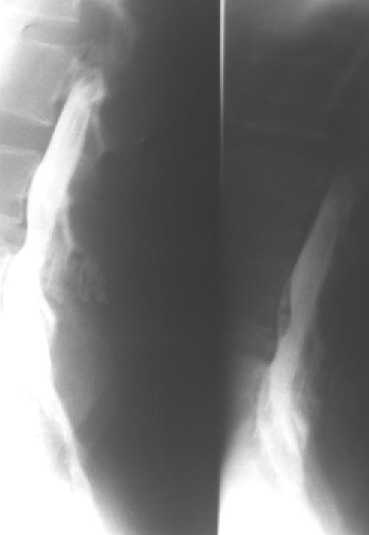

L4-5 Intervertebral disc herniation : with L3 spinal cord tumor